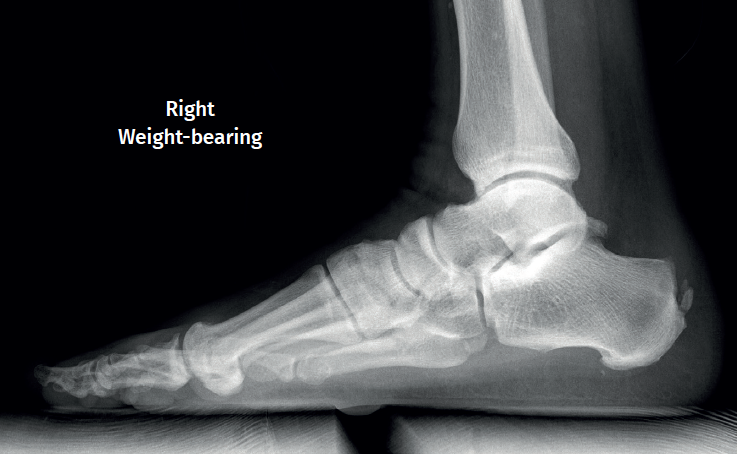

Plain radiography

The dorsoplantar and sagittal views of both feet under loading conditions are indicated, together with the posteroanterior view of the ankles under loading conditions.

Plain radiography under loading conditions is the essential initial diagnostic tool(20). It allows us to assess alignments and dysmetria, to measure angles, to determine the morphology of the calcaneus and its posterior tuberosity, to characterise bone exostosis and increments in thickness of the retrocalcaneal soft tissues, and to plan surgical procedures (Figure 3).

Figure 3. Plain radiography, Sagittal view with weight-bearing. Moderate calcifications in the insertion of the Achilles tendon with intratendinous enthesophyte. Morphological alterations of the posterior tuberosity of the calcaneus.